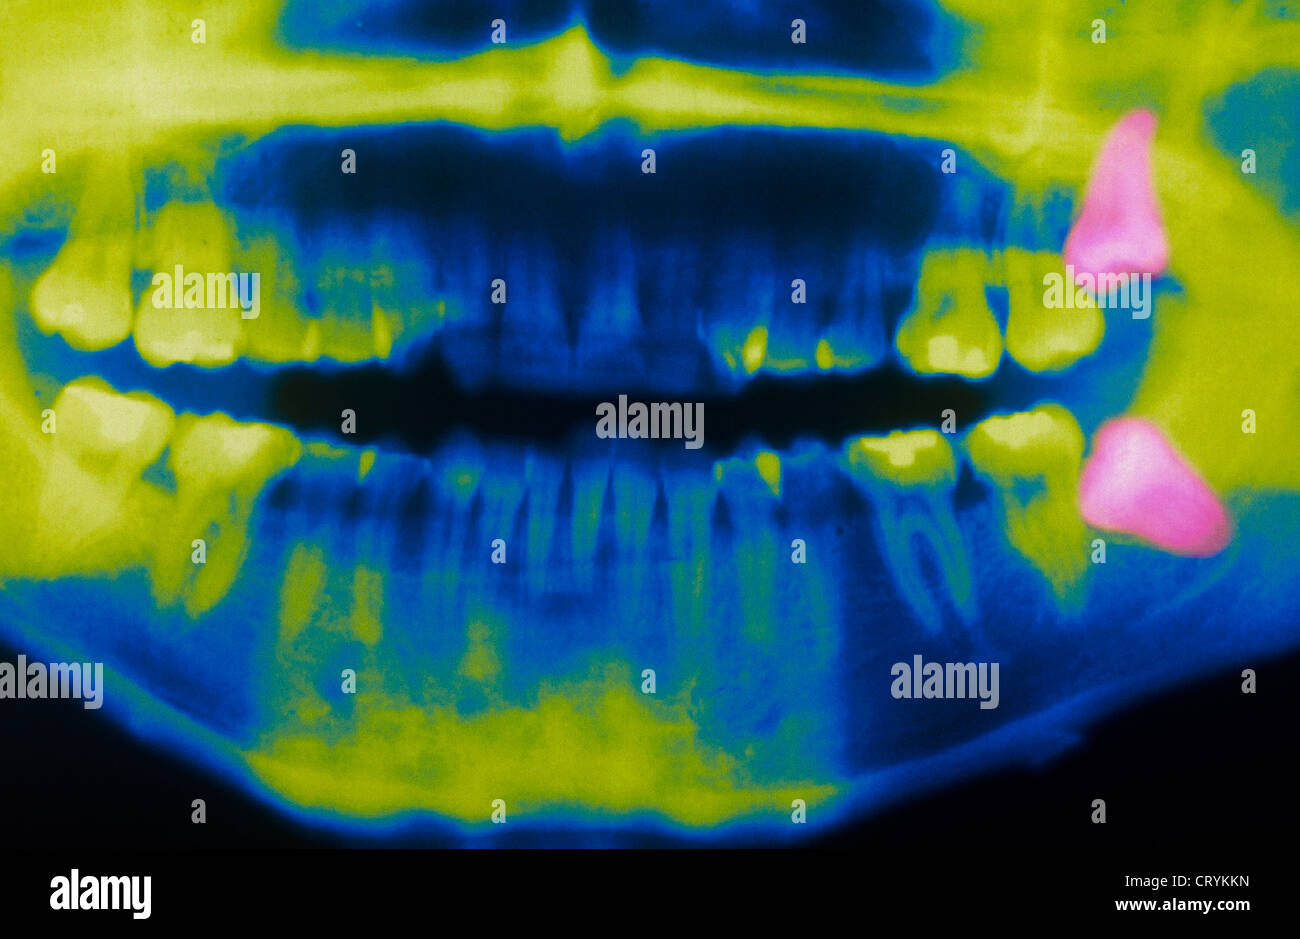

Wisdom Teeth Eruption, Panoral X-ray - Stock Image - C013/1068

Panoramic Dental X-ray With Superior Upper Wisdom Tooth (eight Tooth

www.alamy.comtooth

www.alamy.comtooth

www.shutterstock.comImpacted Wisdom Tooth, Panoral X-ray - Stock Image - C015/2820

www.shutterstock.comImpacted Wisdom Tooth, Panoral X-ray - Stock Image - C015/2820

www.sciencephoto.comwisdom ray tooth impacted

www.sciencephoto.comwisdom ray tooth impacted